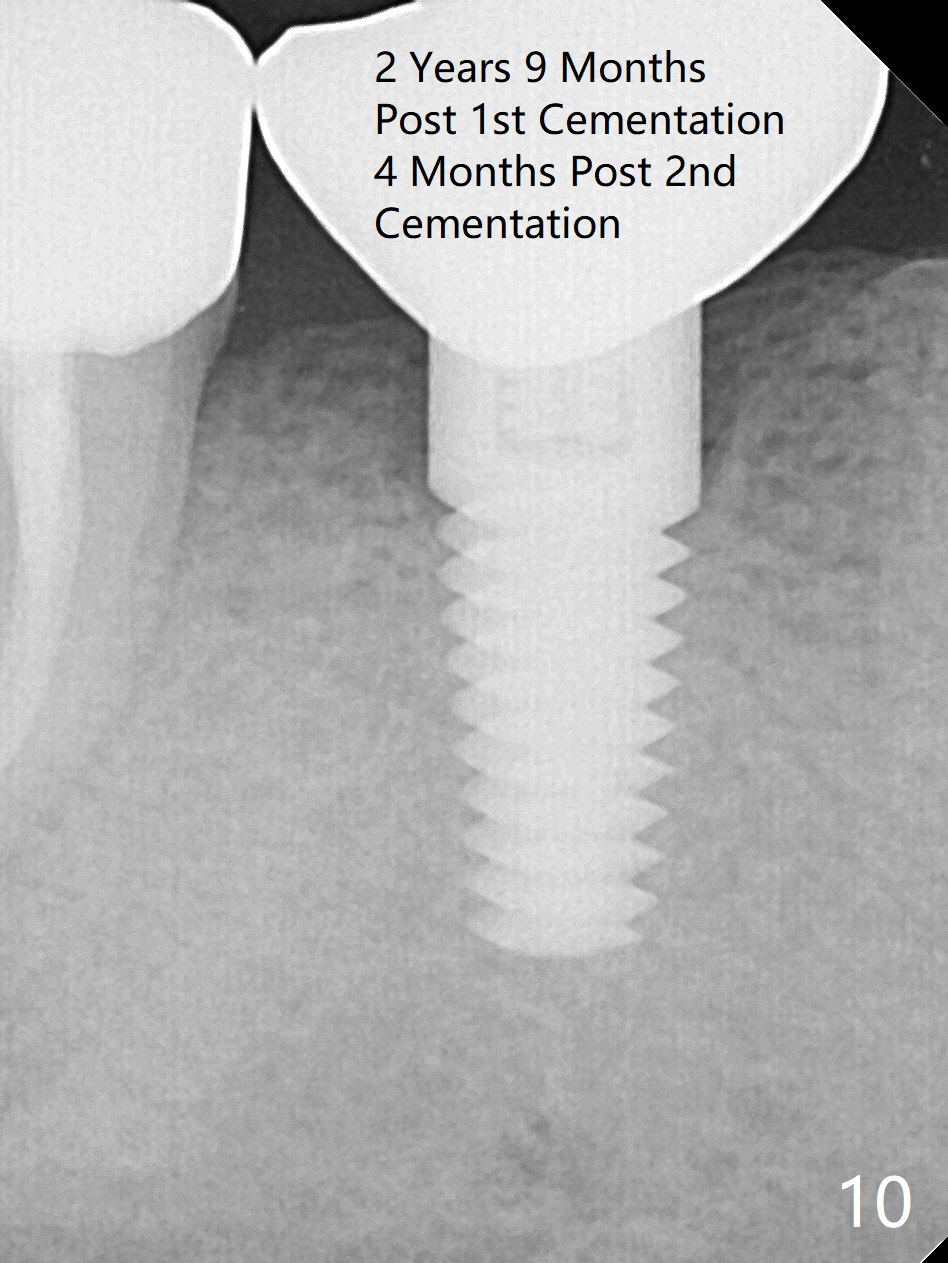

A 47-year-old man has history of bruxism, chipping porcelain from #29-31 FPD (Fig.1). Following sectioning the FPD, osteotomy is created (Fig.2: 5x14 mm drill) for placement of a 5x14 mm tissue-level implant (Fig.3,4). A 4x3 mm abutment (Fig.5 (lingual view) A) with 3 vertical slots (* for increased retention) is placed to retain periodontal dressing. The crown over the implant has dislodged 3 times over 28 months post cementation (Fig.6). It appears that the top of the abutment is too rounded. Clinical exam shows that the abutment height can be more, although the tooth #3 is supraerupted (Fig.7 (orthodontic intrusion is not indicated because of furca infection)).

Pre-impression photos show supraerupted #3 (Fig.7). Clearance is a little more than 1 mm between the mesiopalatal cusp of #3 (Fig.7 *) and the rounded abutment (Fig.8). Removal of the abutment turns out to be easy. Reduction is confined to the opposing tooth (slopes of the cusps). No occlusal reduction is done for the new abutment as mentioned above except for 2 retention grooves. One-mm reduction ring barely passes the occlusal clearance (Fig.9). No cement is applied to the abutment in case a longer abutment may be required. Bone density seems to remain the same or increase after cementation of a new crown (Fig.7). The redo crown remains in place 1 year post cementation.